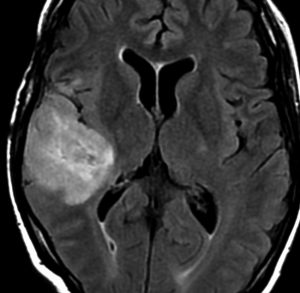

強直発作tonic seizureと夜間の嘔気発作で発症した女の子の乏突起星細胞腫です。海馬鉤と扁桃体を侵す内側側頭葉神経膠腫 mesial temporal gliomaと呼ばれる腫瘍です。特に小児に難治性てんかんを生じることで有名です。

T2強調画像とフレア画像でまだらな高信号を示しますが,境界は比較的明瞭です。限局性グリオーマ localized gliomaと呼ばれるタイプです。

CTでもMRIでも全く増強されません。

術後のMRIです。腫瘍は全摘できていて再発はありません。手術でとても大切なことは,てんかん原性のある海馬鉤の腫瘍を摘出するだけではなくて,扁桃体切除 amygdalectomyも加えることです。それによって症候性てんかんをmedication freeにもっていける可能性があがります。扁桃体は片側(この場合は左)切除しても症状は出ません。